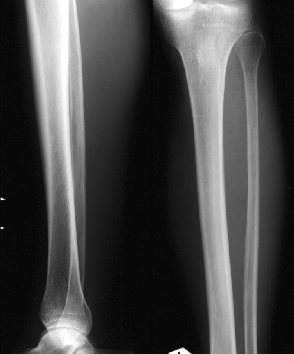

РОЗПІЗНАЙТЕ КІСТКУ. ПЕРЕЛОМ ЯКОЇ ЇЇ ЧАСТИНИ ВИ БАЧИТЕ НА РЕНТГЕНОГРАМІ?

ДЕ ВИ БАЧИТЕ КІСТКУ, ЩО РОЗТАШОВАНА З ЛАТЕРАЛЬНОЇ СТОРОНИ ГОМІЛКИ?

ЯКИЙ СУГЛОБ УТВОРЮЮТЬ ТАКІ КІСТКИ: FEMUR, FIBULA ТА TIBIA ?

РОЗПІЗНАЙТЕ СУГЛОБ, ЯКИЙ ЗАБЕЗПЕЧУЄ РУХИ ГОМІЛКИ.